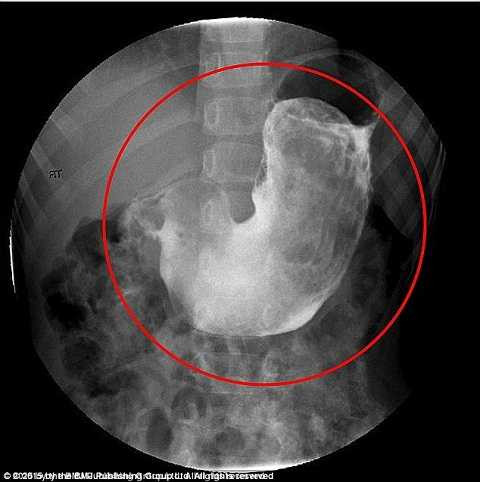

6. Bé gái với sở thích ăn tóc

Bác sĩ đã phát hiện ra một khối tóc cuộn tròn bên trong dạ dày của nột cô bé 5 tuổi khi khám tại bệnh viện vùng Adelaide, Australia khi bắt đầu có triệu chứng đau bụng được vài tuần. Bé gái chỉ thích ăn tóc mà không thèm ăn bất cứ thức ăn nào.

Đây là một biểu hiện của hội trứng trichotillomania (thích ăn tóc). Cuộn tóc khá to do các sợi bện chặt với nhau có kích thước tương đối lớn kéo dài đến tận ruột già. Nếu phát triển thêm, nó có thể gây viêm loét dạ dày rất nghiêm trọng nhưng các bác sĩ đã phẫu thuật thành công và lấy ra cuộn tóc với trọng lượng 125 gam.